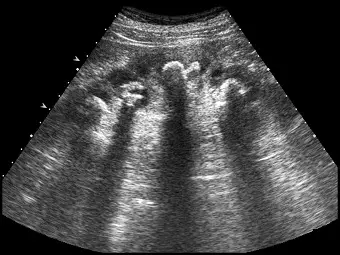

腎臟超音波掃描,發現多處的腎盞(calyxes)呈現高回音性病灶併有後方回音陰影(posterior acoustic shadows)如下圖,最有可能的診斷為何?

題目所附的腎臟超音波影像中,可以清楚觀察到以下關鍵特徵:

- 高回音性病灶(Hyperechoic lesions):在腎臟內部的集尿系統(腎盂與多處腎盞)區域,可見呈現強烈白色(高回音)的結構分佈。

- 後方回音陰影(Posterior acoustic shadows):這些高回音病灶的後方,出現了明顯的黑色無回音帶(聲影,acoustic shadowing)。這是因為超音波被堅硬組織(如鈣化或結石)強烈反射與吸收,聲波無法穿透所致。

- 分佈形狀:病灶沿著腎臟集尿系統(腎盂並延伸至多個 calyxes)分佈,呈現分支狀(鹿角狀)的外觀。 綜合以上特徵,此為典型的「鹿角結石(Staghorn calculus)」超音波表徵。

- (A) 鹿角結石(staghorn stone):正確。結石在超音波下的典型表現為強高回音(hyperechoic)病灶,並伴隨明顯的後方回音陰影(posterior acoustic shadow